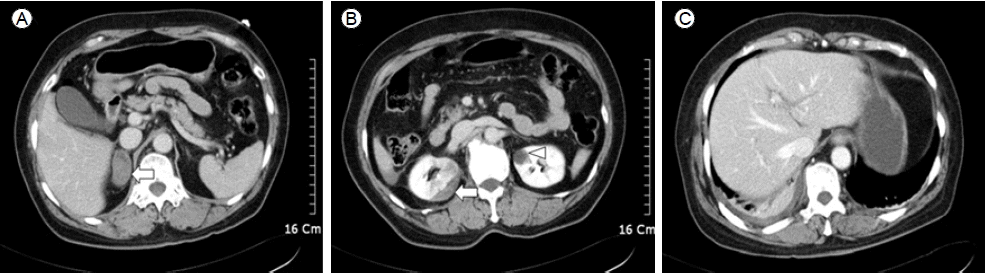

방사선 검사: 단순 흉부 방사선 검사에서 우측 3-9,11,12번 갈비뼈 골절 소견과 우측 흉곽에 삼출액 소견이 관찰되었다. 심장의 크기는 정상이었으며 폐부종 소견은 없었다. 복부 전산화 단층촬영에서 우측 신장의 1.5 cm의 피막하 혈종과 우측 부신의 4 cm의 혈종, 간의 열상과 복강 내 소량의 혈액이 관찰되었다(Fig. 1A and 1B). 신동맥 협착증이나 혈종에 의한 신동맥의 직접적인 압박 소견은 관찰되지 않았다(Fig. 1C).